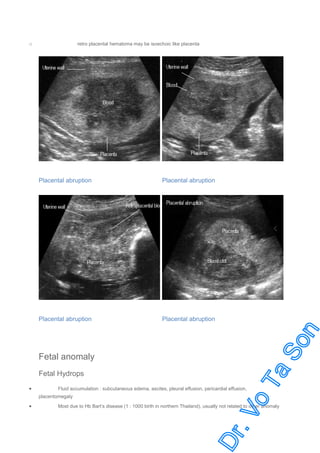

Placental Abruption

cystic, complex, or hypoechoic areas may be seen between placenta and uterine wall

reveal type may be not diagnosed

Placental thickening

retro placental hematoma may be isoechoic like placenta

Fetal anomaly

Fetal Hydrops

Fluid accumulation : subcutaneous edema, ascites, pleural effusion, pericardial effusion,

Most due to Hb Bart’s disease (1 : 1000 birth in northern Thailand), usually not related to other anomaly